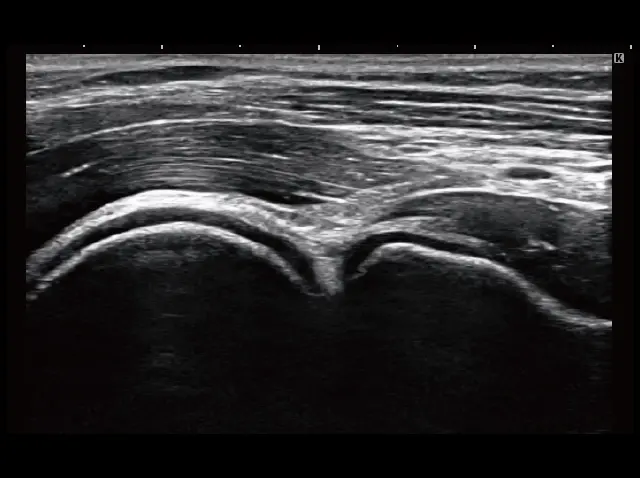

イメージギャラリー

イメージ画像を表示する